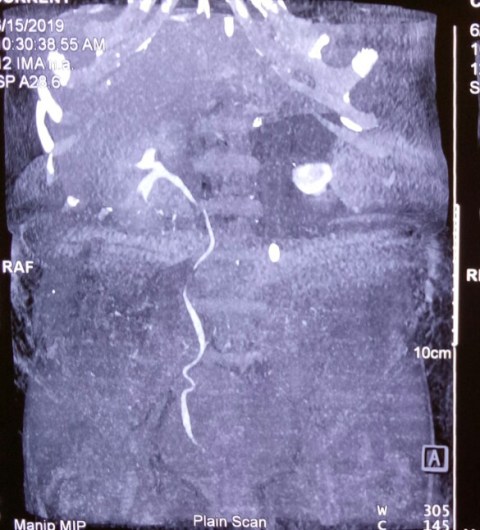

Another lap chole landing up in trouble. A young 30 years old male underwent a very difficult lap chole due to the frozen Calot’s triangle and a very thick walled gall bladder. Postoperatively had a bile leak which was 200 cc on the first postoperative day and then continued to decrease in amount gradually drying up in 18 days. MRCP shown below reported a small collection and a ? kink and narrowing at the site of cystic duct-CBD junction. Was it a cystic duct blow-out?